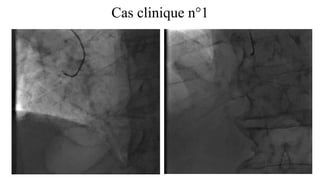

Cas clinique n°1

• Réalisation d’une coronarographie par l’artère radiale droite en matériel 5F

CX prox sub occlusive

Double bourgeon calcaire TC

• Angioplastie complexe

• Calcifications sévères

• Atteinte du TC

• CX sub occlusive, calcifiée et forte angulation

• Patient âgé, à haut risque hémorragique

• Quelle stratégie? Quels outils?